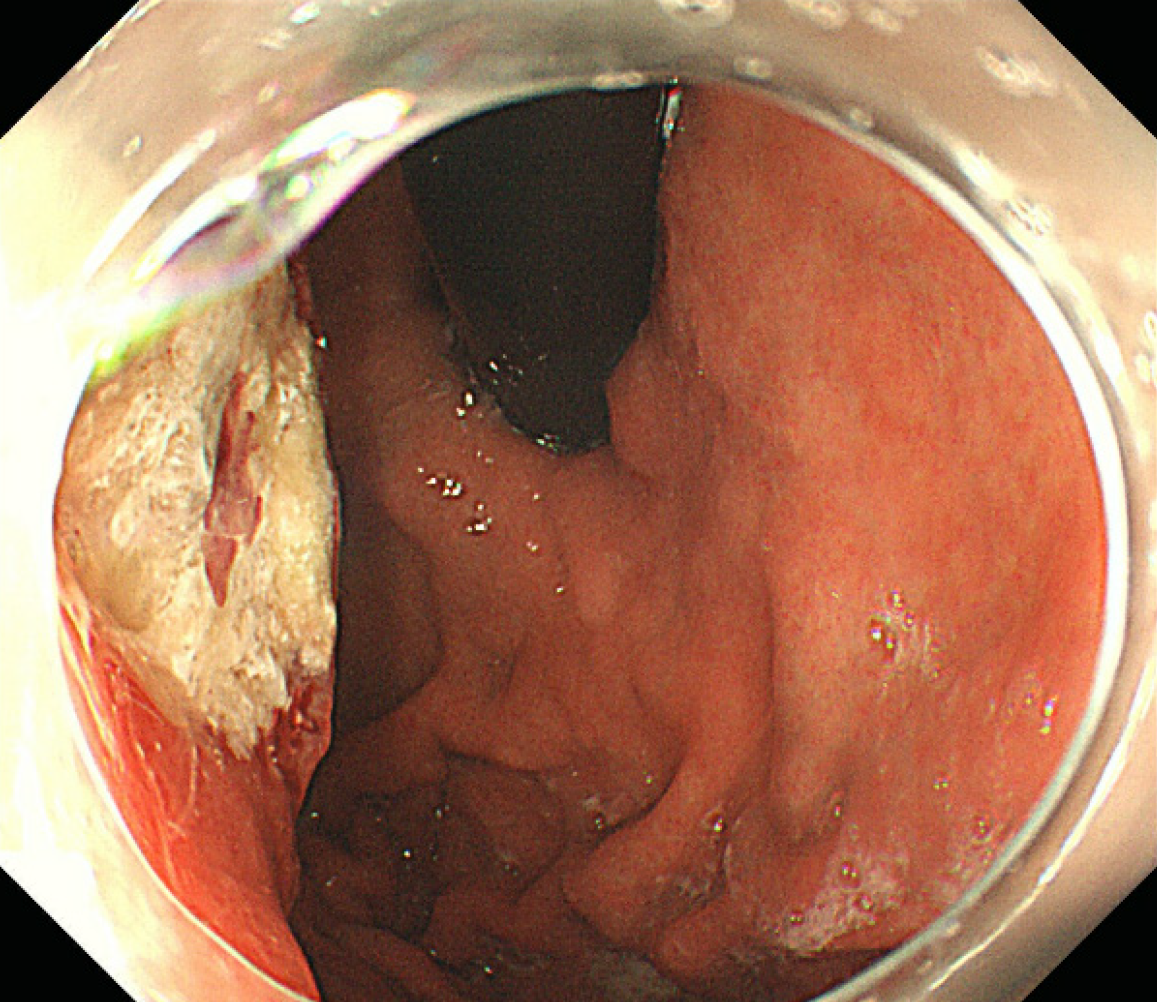

Small blue round cells infiltrated all layers of the gastric wall, and nuclear mitosis was visible (Figure 3). Immunohistochemically, the tumor cells diffusely expressed cytokeratin (CK), synaptophysin, cluster of differentiation 56, and INSM1 indicating that the tumor was a gastric neuroendocrine carcinoma (NEC) (small cell carcinoma) (Figure 4). CK20, p40, CK5/6, chromogranin A (CgA), and somatostatin receptor 2 were all negative. The Ki67 index was approximately 95%. p53 was mutant (nonsense mutation). RB1 showed a loss of expression while INI-1 and BRG1 showed preserved expression. The combined positive score of PD-L1 was 1.

Histologically, the tumor exhibited a nest-like and solid sheet arrangement, with no evidence of glandular differentiation. The cell morphology of GSCC can be round or oval, with scant cytoplasm. Nucleoli are not prominent, and necrosis is commonly observed. Mitotic figures are frequently seen. As a tumor with small blue round cells, it needs to be differentiated from the following tumors: (1) Ewing’s sarcoma or peripheral primitive neuroectodermal tumor: EWS-FLI-1 gene fusion can be detected by reverse transcription-polymerase chain reaction; (2) Alveolar rhabdomyosarcoma: This tumor shows diffuse positivity for MyoD1, myogenin, and desmin. Characteristic chromosomal translocations t (2; 13) and t (1; 13) are observed in this tumor; (3) Lymphoma: Tumor cells are mainly round and express lymphoma markers such as leukocyte common antigen. Immunohistochemically, synaptophysin, CgA, and insulinoma-associated protein 1 are particularly significant and can help diagnosis; and (4) Metastatic small cell carcinoma from the lung: Tumors from the lung express thyroid transcription factor-1 more frequently, and chest computed tomography can identify the primary lesion.